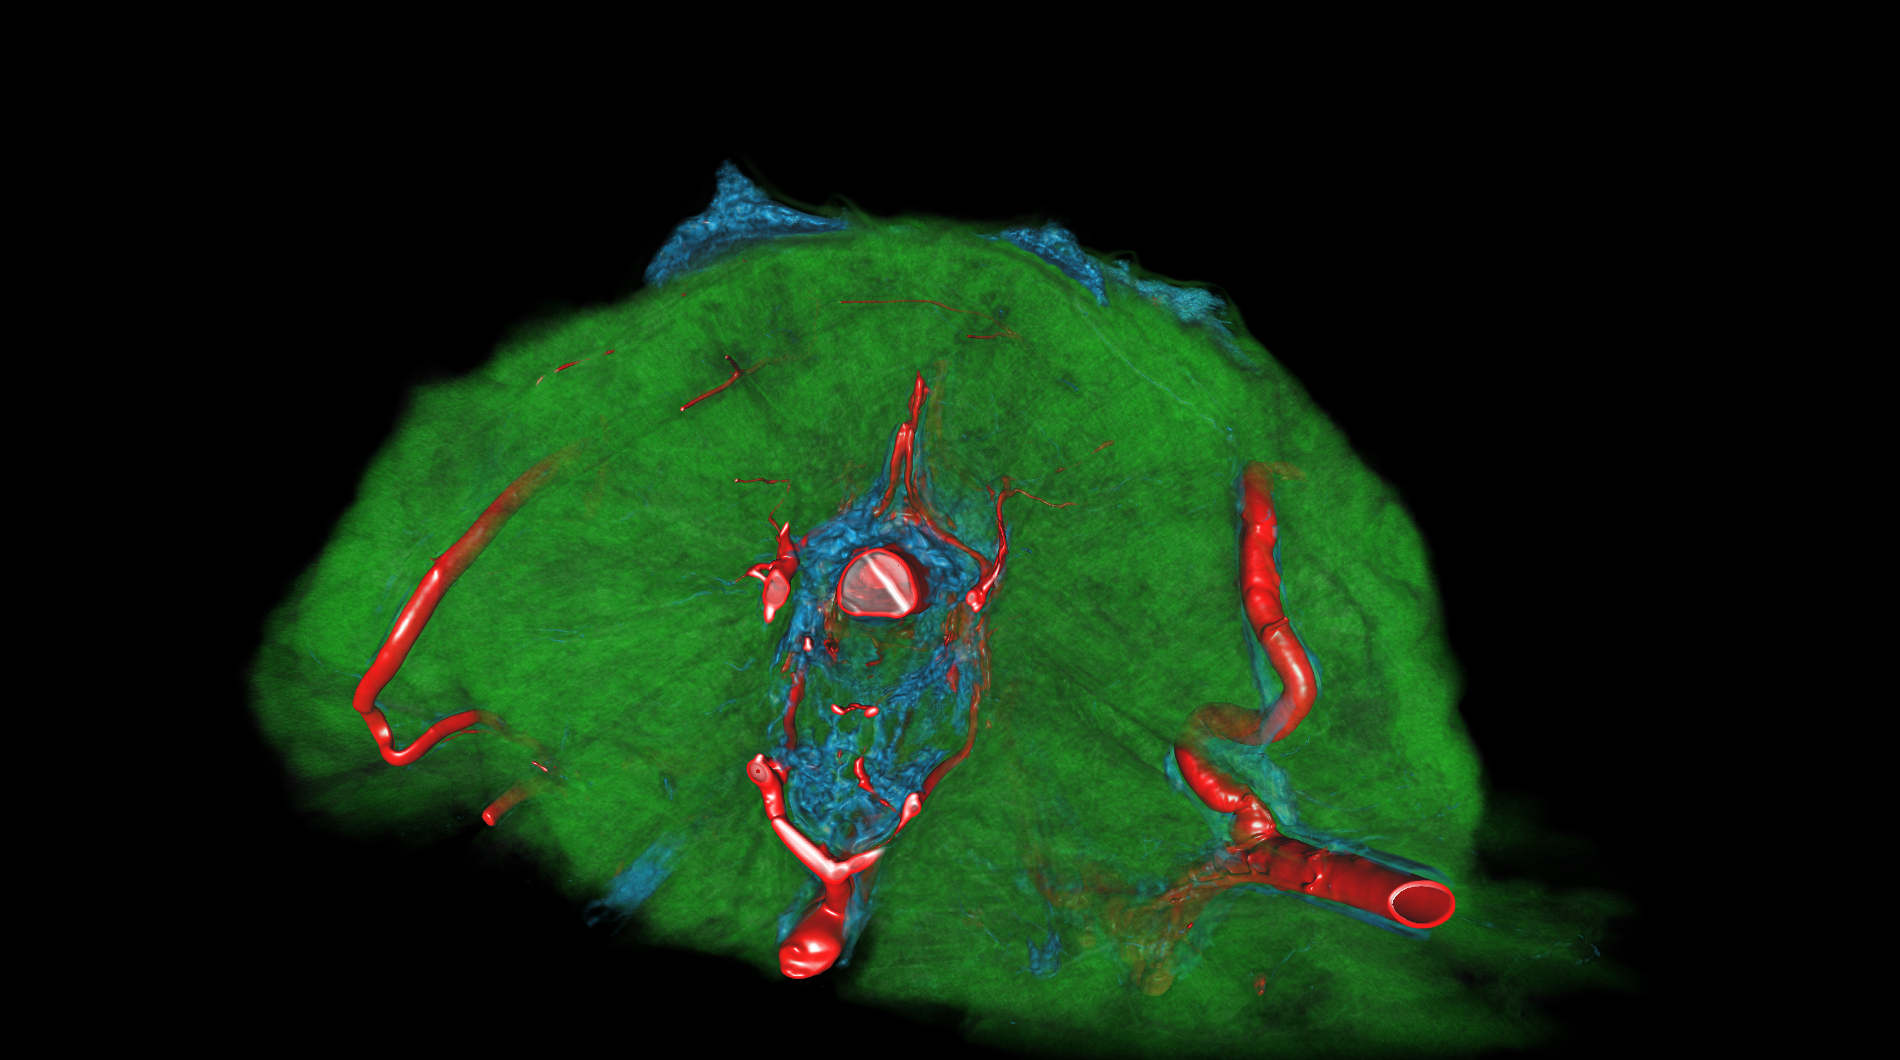

medical-03

The medical-03 viewset demonstrates the performance of several medical visualization volume rendering techniques. The first is "slice rendering", where many 2D slices are projected through the volume and composited on the screen. The second is "raycasting" where rays are projected through the volume accumulating the final pixel color. Two different transfer functions are used: 1D, where the density is used to look up each voxel color, and 2D, where density and gradient magnitude are used to look up each voxel color. A clipping plane is used in several tests. The Tuvok visualization library is used for rendering.

medical-03 composite score: 25.67

The composite score is a weighted geometric mean of the subtest scores. See the table below for subtest weights and FPS scores for this run.

Subtest results

Click on each thumbnail image below to display the subtest's screen grab.

The results table above includes the details about each test within a viewset. Viewsets are often comprised of many tests which produce a frame rate. Frame rate is computed as the average Frames Per Second (FPS), or the total number of frames rendered divided by the time in seconds to render those frames. These FPS values are then used to compute the composite score using the weights for each test.